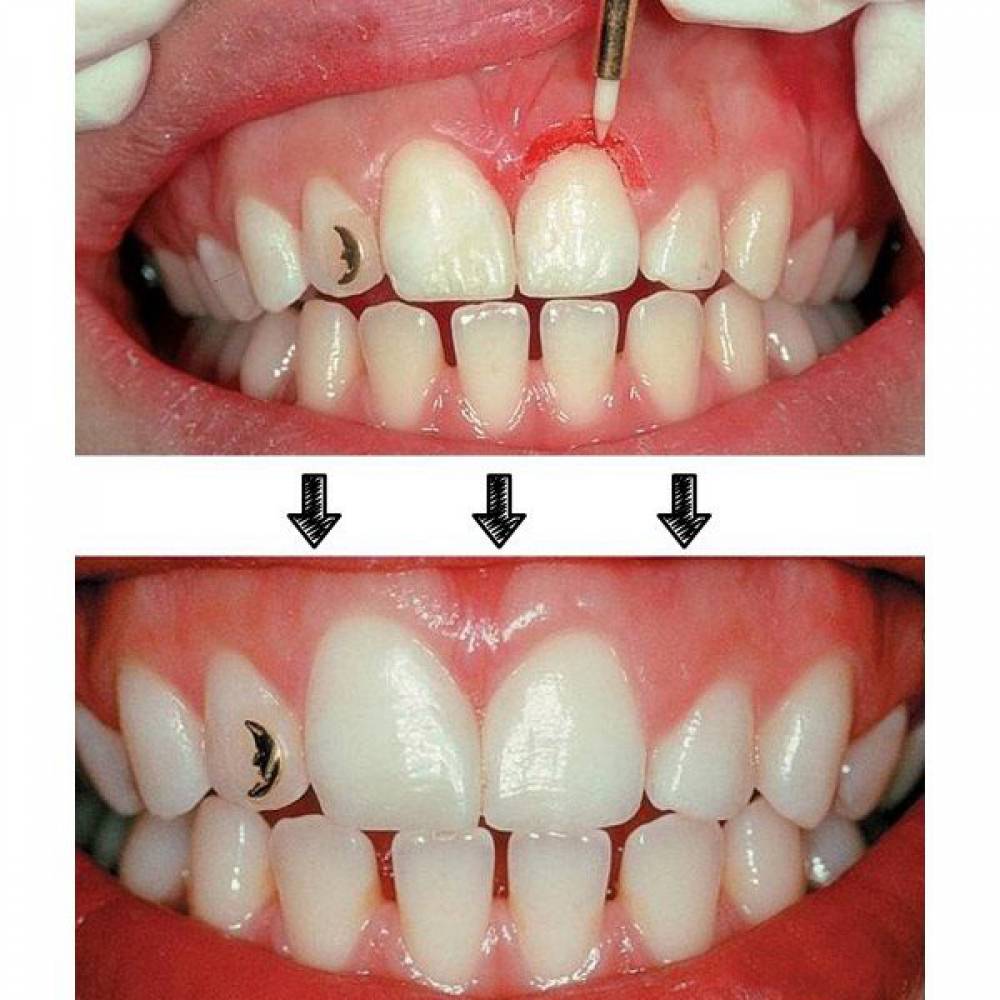

| کاربرد | برداشت لثه (Papilectomy) – برداشت بافت هاى مزاحم نشست روکش – باز کردن سالکوس قبل از گرفتن قالب – آشکار سازى بخش هاى از ایمپلنت که دیده نمى شود و دندانها نهفته |